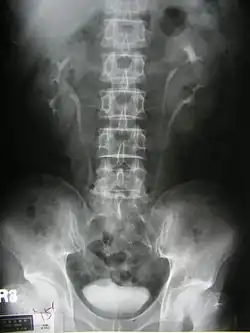

Duplicated ureter

Duplicated ureter or duplex collecting system is a congenital condition in which the ureteric bud, the embryological origin of the ureter, splits (or arises twice), resulting in two ureters draining a single kidney. It is the most common renal abnormality, occurring in approximately 1% of the population.[1][2]